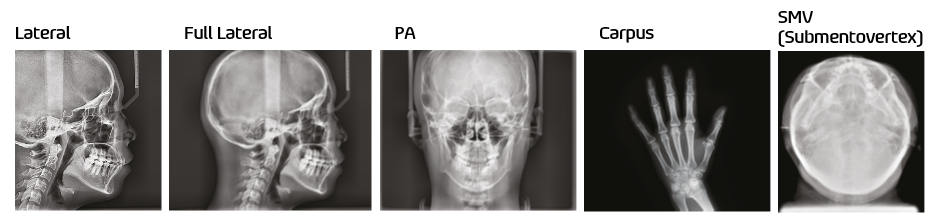

PaX-i Plus provides the most precise and high quality panoramic image by innovative imaging process and accumulated experience in dental imaging from VATECH. It improves your diagnostic accuracy with increased treatment planning and patient satisfaction.